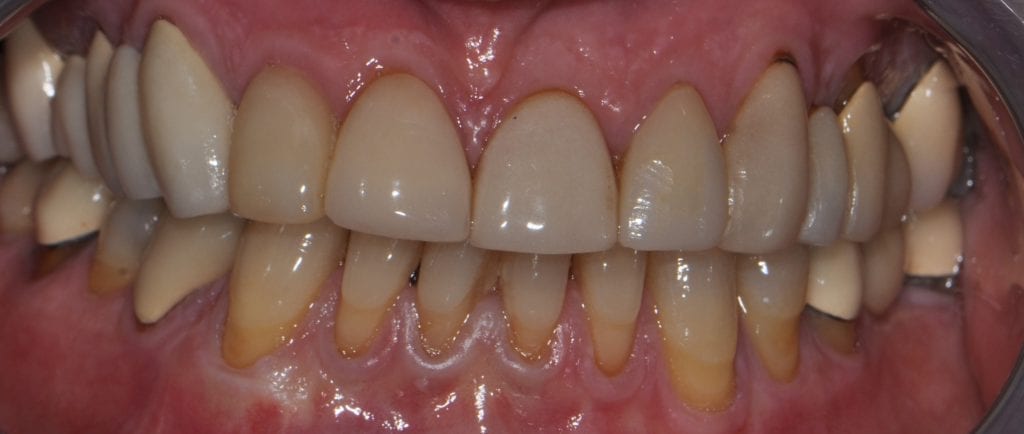

Pre-existing restorations that warranted replacement with an increase in vertical dimension.

Pre-existing restorations that warranted replacement with an increase in vertical dimension. The upper and lower arch were captured with the medit I500 and articulated together with enough clearance to accommodate new restorations and to restore the patient to an ideal tooth position.